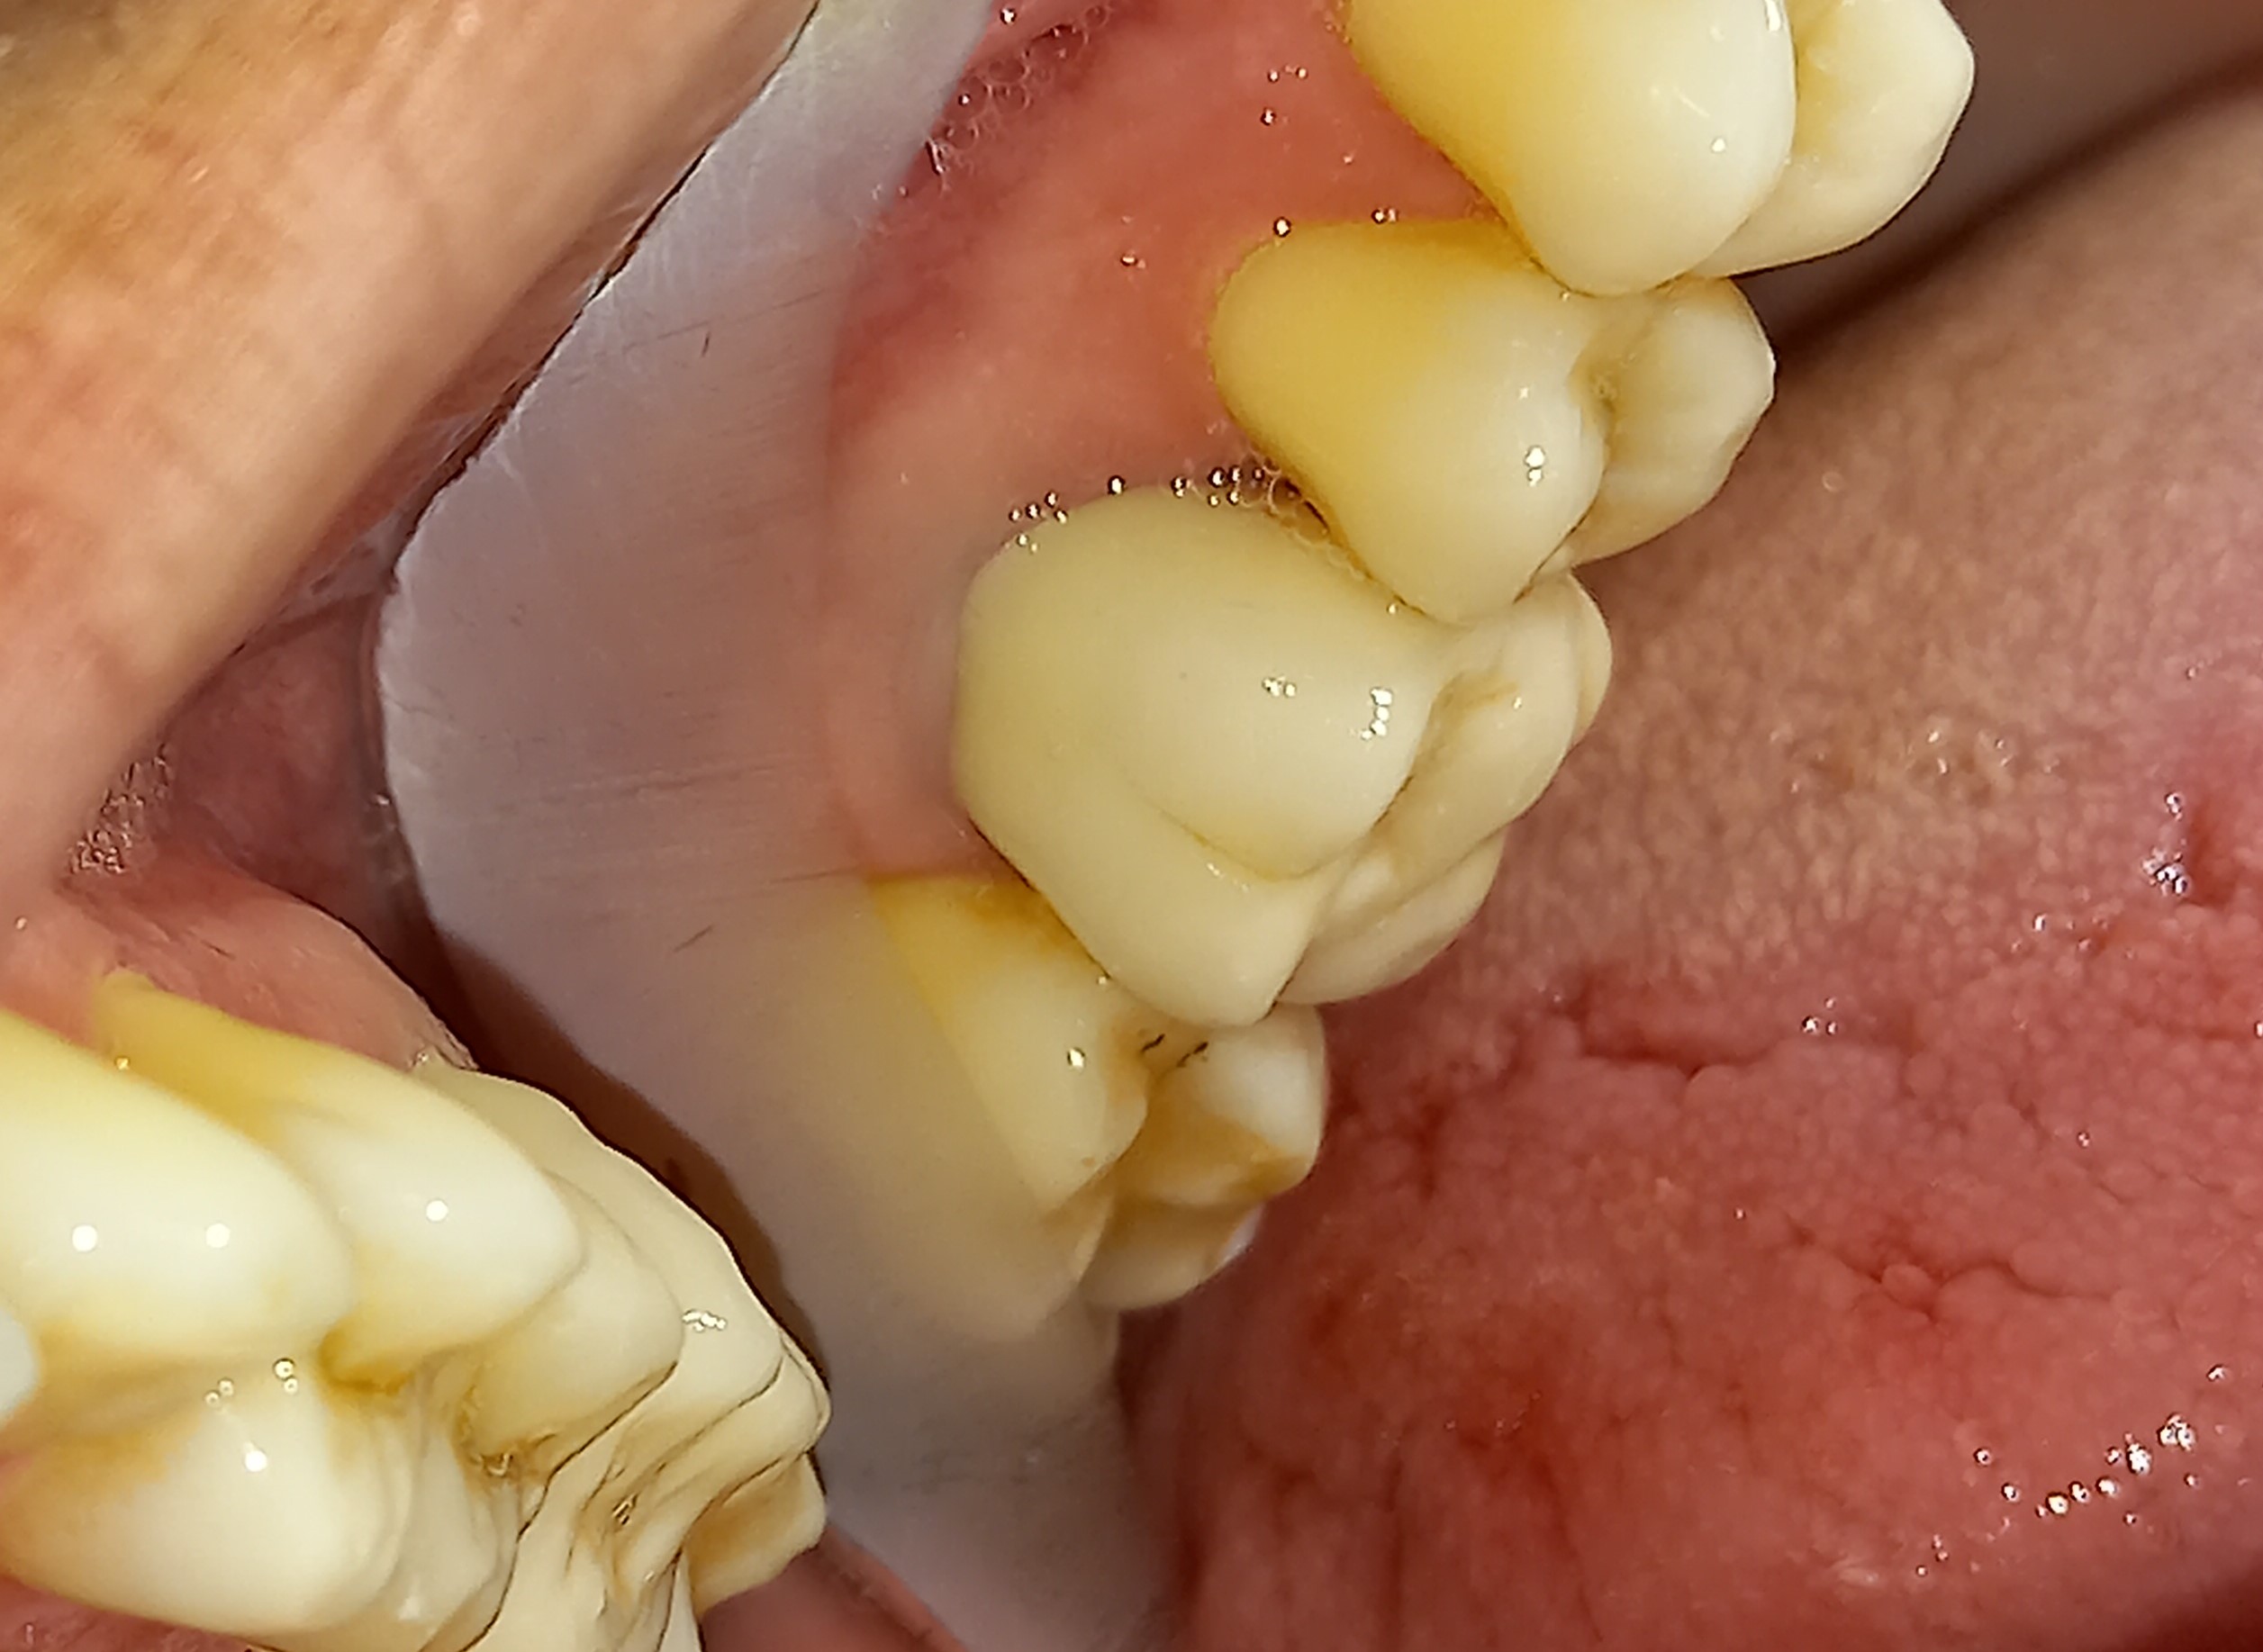

Τελική κλινική εικόνα του ολοκεραμικού ένθετου στον προγόμφιο